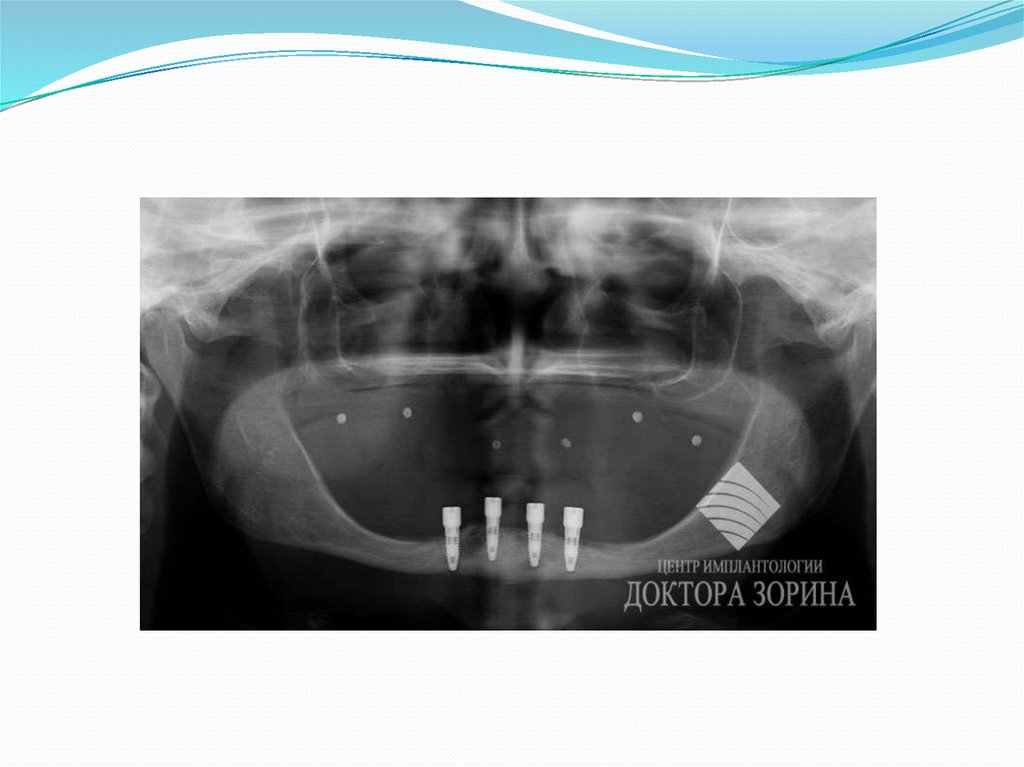

10. Тіссізденген жақтың рентген көрінісі.

УНИВЕРСИТЕТ ИМЕНИ С.Д.АСФЕНДИЯРОВА